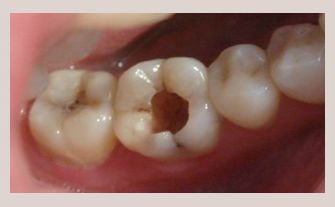

牙齒是人類最堅(jiān)硬的器官,但是只要有損壞,沒有及時(shí)修補(bǔ),到了一定的時(shí)間,就會(huì)損壞牙齒的神經(jīng)組織,從而引發(fā)“疼痛”。

怎么補(bǔ)?傳統(tǒng)的補(bǔ)牙方法就是把蛀牙的地方磨掉,然后再補(bǔ)上材料,最后進(jìn)行拋光。

傳統(tǒng)方法方便快捷,能一次完成,但由于傳統(tǒng)的補(bǔ)牙是在口內(nèi)一次性完成的,整個(gè)的操作過程受到口腔唾液,以及醫(yī)生在口腔內(nèi)操作空間太小等一些客觀的,難以避免的因素影響。最終使得補(bǔ)上去的牙齒壽命不長,還有可能引發(fā)脫落和繼發(fā)齲等癥狀。并且像面積較大的齲壞和特殊部位的齲壞就算補(bǔ)了牙也不耐用。